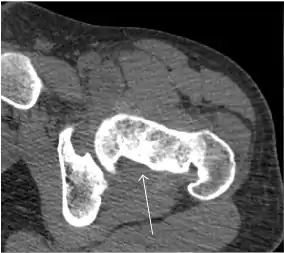

Synovial chondromatosis can be confidently diagnosed by X-ray when calcified cartilaginous chondromas are seen. However, other synovial proliferative processes, such as pigmented villonodular synovitis, require MRI for accurate diagnosis, although noncalcified synovitis can be suspected in radiographs by indirect signs, such as soft tissue swelling and/or erosions in the femoral head, femoral neck, or acetabulum (Figure 7).[1]

Figure 7:

- Axial CT image of pigmented villonodular synovitis eroding the posterior cortex of the femoral neck.[1]

- Sagittal T2* gradient echo image showing a posterior soft tissue mass with hypointense areas secondary to hemosiderin deposition.[1]

- X-ray of synovial chondromatosis.[1]

- CT of synovial chondromatosis.[1]

In synovial proliferative disorders, MRI demonstrates synovial hypertrophy. In the case of PVNS, characteristic foci of low signal intensity related to hemosiderin deposition are better seen on gradient echo T2* images (Figure 7). In the case of synovial osteochondromatosis, the synovial hypertrophy is accompanied by intermediate signal cartilaginous loose bodies and/or low signal calcified loose bodies.[1]